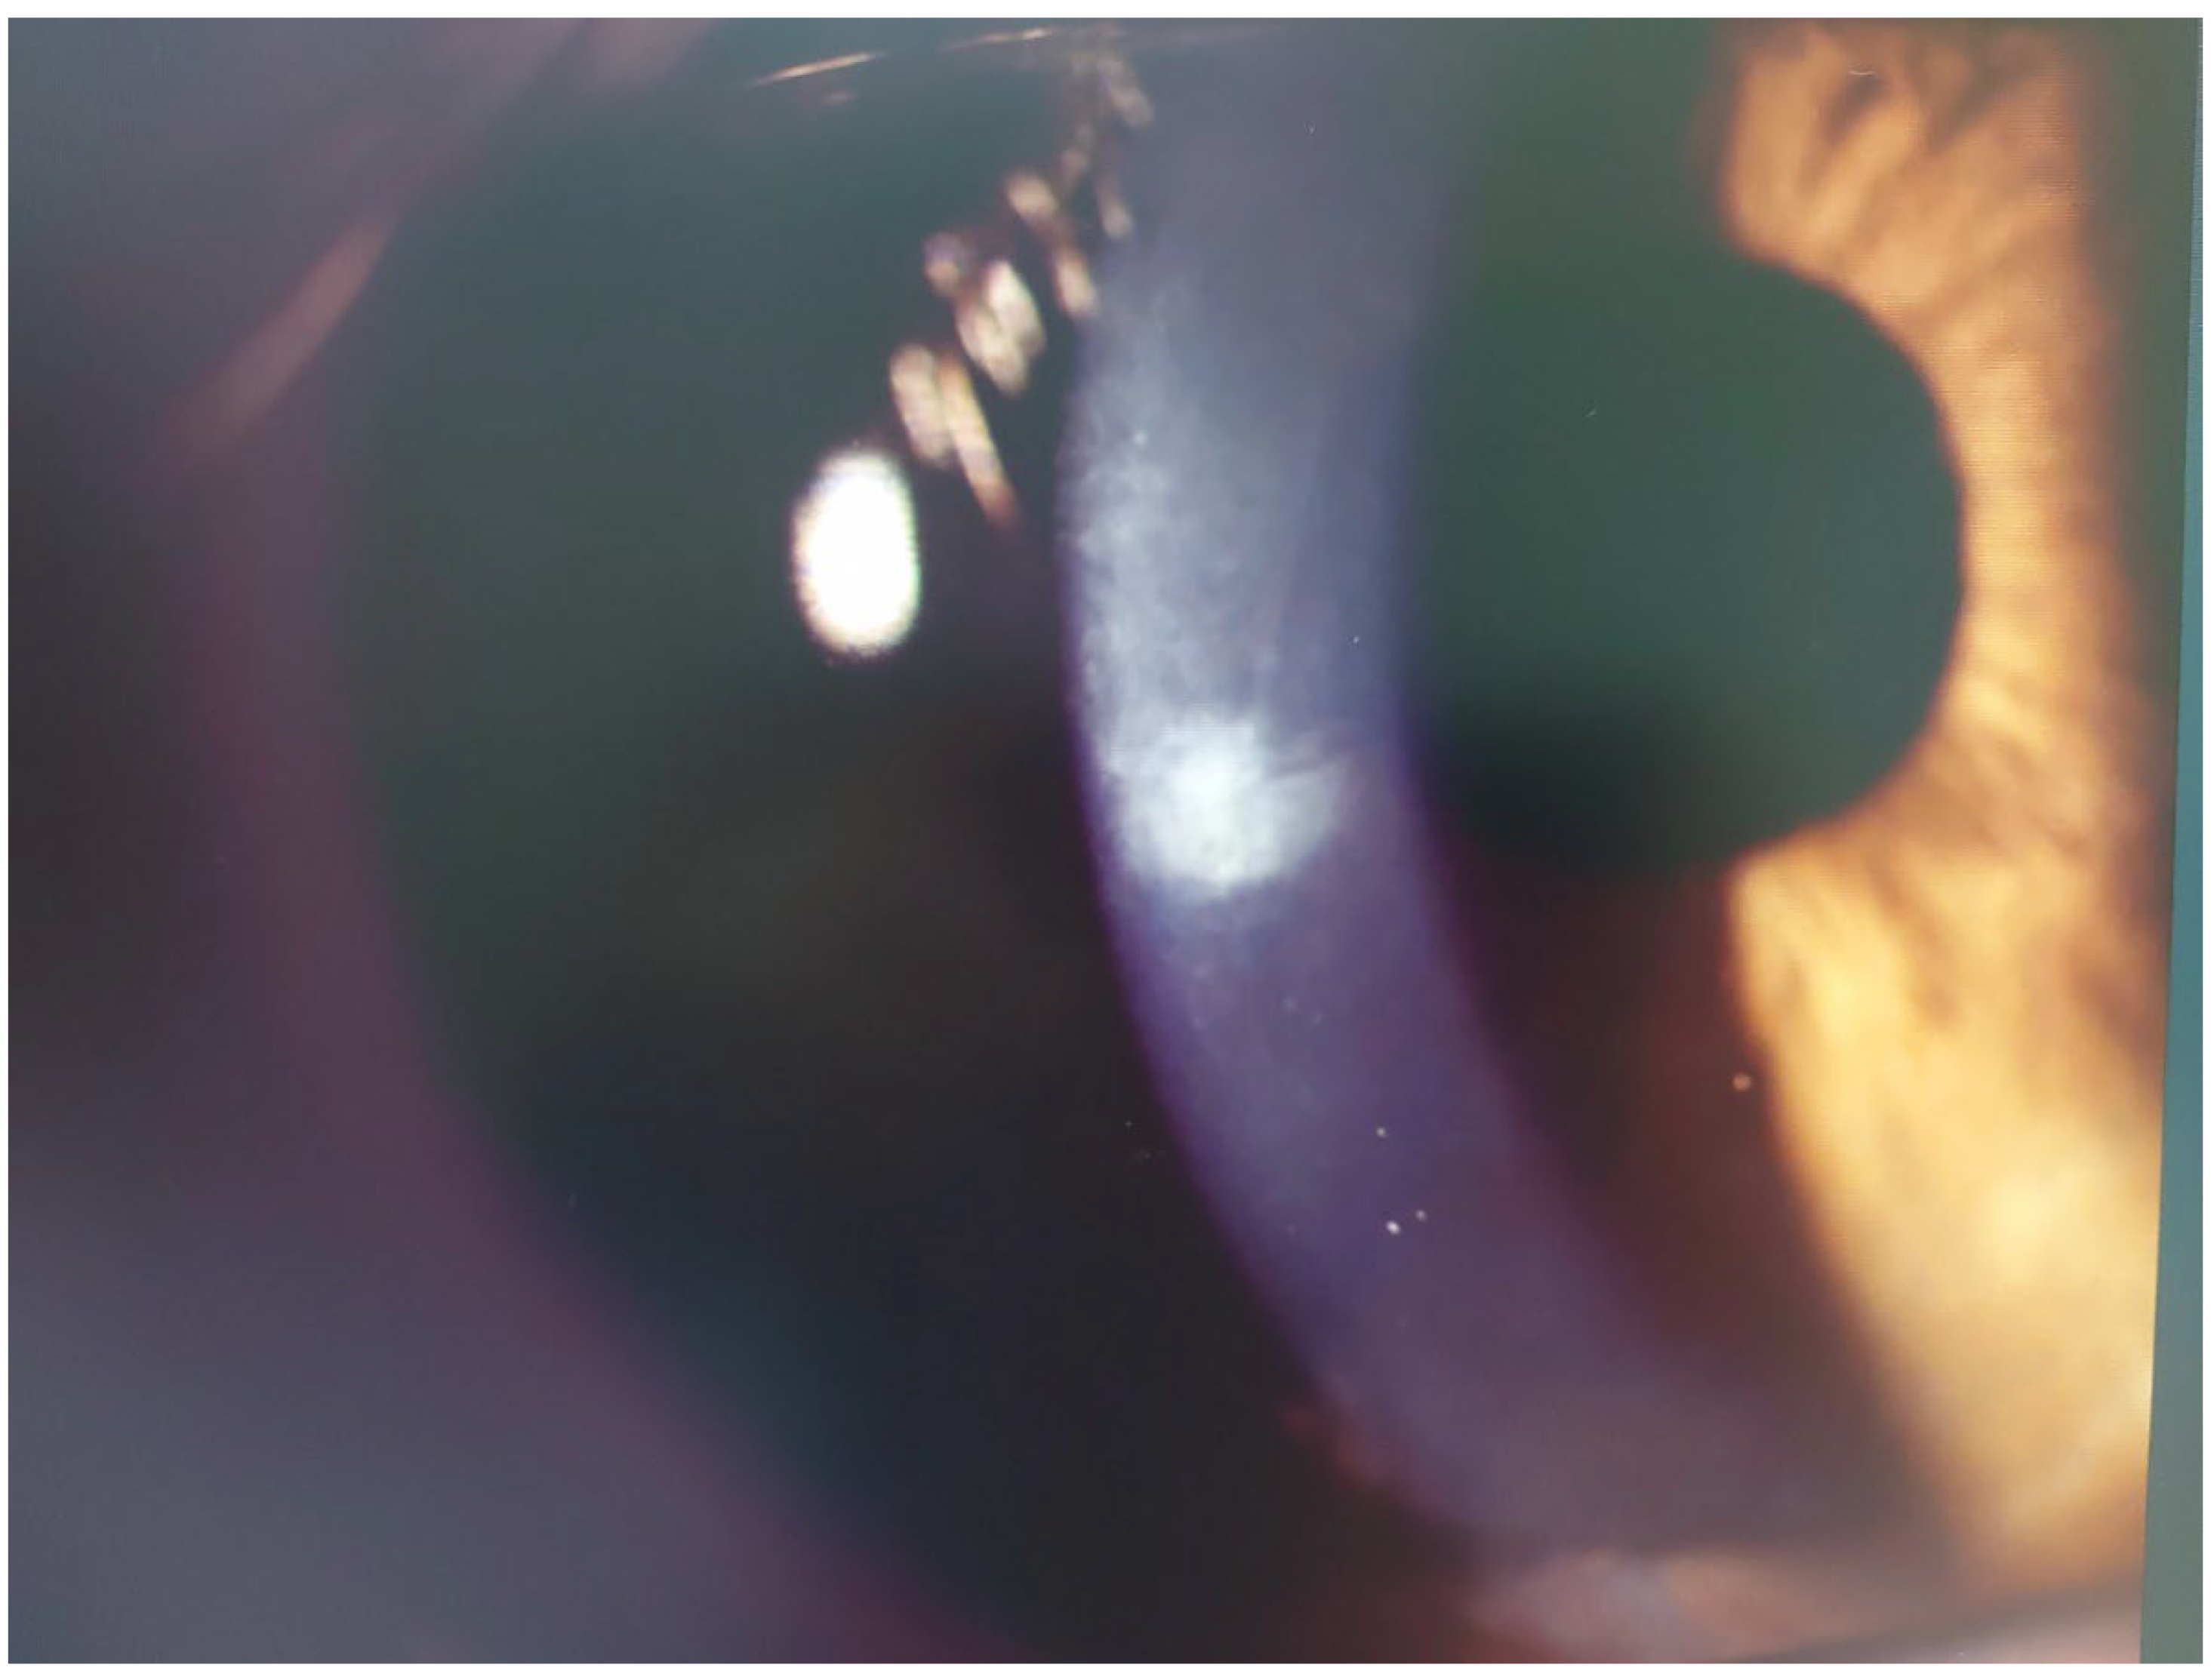

Infectious Keratitis Post-KLEx

Patient #3

Patient #4